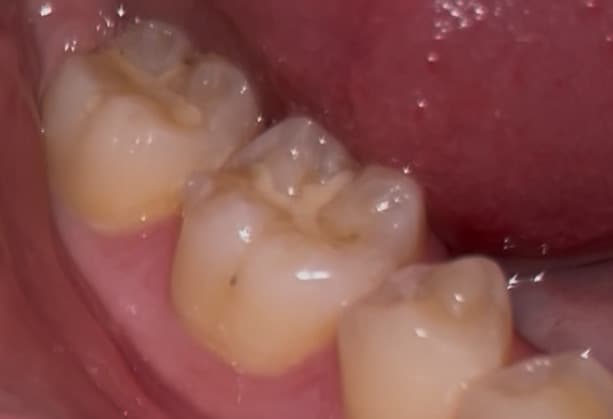

이정도 치아 깨진거 치료 받아야할까요? +충치

2. 옆면에 있는 충치 상태도 좀 봐주세요 ㅠㅠ

• 2번 째 사진

사진으로 봤을 경우에 치아가 깨진 것보다 부분 부분 충치가 보이고 있습니다. 충치가 있는 부분엔 이물질이 남아 있게 되어 충치가 진행될 수 있으니 충치가 있는 부분은 치료를 해주는 것이 좋습니다.

깨진 정도가 크진 않으나 한번 깨졌던 치아는 그 부위가 씹을때 힘이 강하게 가해진다는 것이므로 또 추가적으로 깨질 우려가 큽니다. 전반적으로 상태 보고 레진으로 떼우거나 아니면 크라운을 씌워주면 좋을 것 같습니다.

옆면 충치 큰 편은 아닙니다.